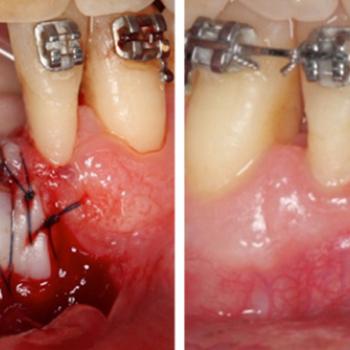

La cirugía mucogingival reconstructiva alrededor de implantes corrige los defectos de la morfología, posición y/o cantidad de encía queratinizada alrededor de los mismos. El documento que mostramos a continuación presenta el caso clínico de un paciente varón de 55 años de edad, exfumador de hace 2 años, con antecedentes de periodontitis crónica moderada generalizada y avanzada localizada tratada y, actualmente en fase de mantenimiento. El paciente no refería ningún antecedente médico de interés odontológico ni alergias conocidas.

El caso clínico es un buen ejemplo de cómo dotar de una buena cantidad de encía queratinizada unos implantes dentales con una emergencia en mucosa alveolar. De esta forma puede mejorarse la higiene periimplantaria diaria y disminuir así  las posibilidades de aparición de patología periimplantaria en un futuro.